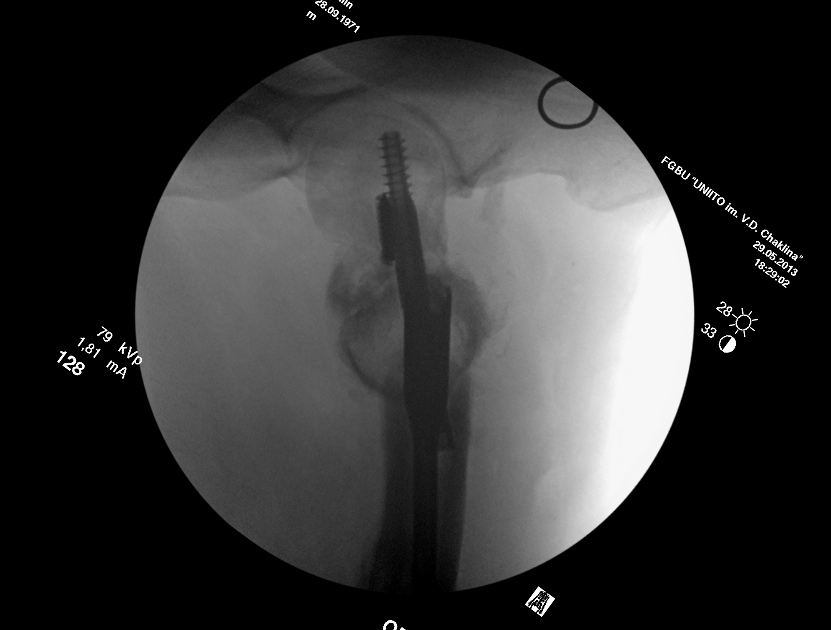

Насчет ревизионного штифтования - вот пример, вчера сделали.

Имя     : 3.jpg

Тип     : image/jpeg

Размер  : 52472 байтов

Url     : http://weborto.net:8080/pipermail/ortho/attachments/20130531/0a9354ad/attachment-0006.jpg